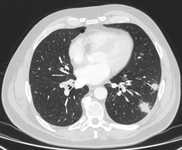

Corte de tomografia computadorizada (TC) com configuração de tecidos moles, mostrando hamartoma de pulmão direito, como achado incidental em paciente assintomático. Observe a calcificação central e vários pequenos pontos de gordura dentro do nódulo. Este nódulo permaneceu estável durante um período de 12 anos, não tendo sido necessária nenhuma intervenção

Do acervo de Dr. George Tsaknis, MD, PhD, FRCP (Londres), MRQA, MAcadMEd, PGCert; usado com permissão